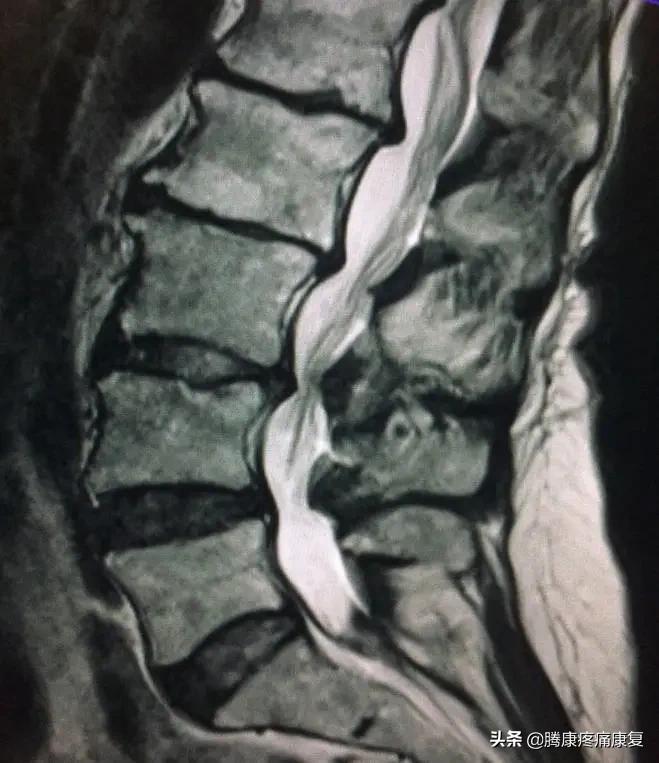

随着年龄增长,腰椎发生退行性改变,椎间盘退变,椎间隙变窄,周围韧带松弛,椎体间骨赘增生,突入椎管导致椎管容积变小;小关节退变,关节囊松弛,小关节增生,上关节突增生导致侧隐窝狭窄,下关节突增生向椎管内聚,导致中央管狭窄;椎板及黄韧带增生肥厚,导致中央椎管狭窄。

此外,合并腰椎间盘突出、退变性滑脱也会导致椎管狭窄。

腰椎管狭窄根据部位分型

①中央型椎管狭窄

即椎管中矢径狭窄,当矢状径<10mm为

绝对狭窄,10~13mm为相对狭窄。